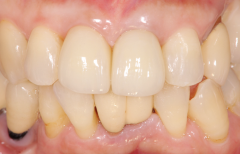

インプラント埋入後、セラミック冠をセットした症例